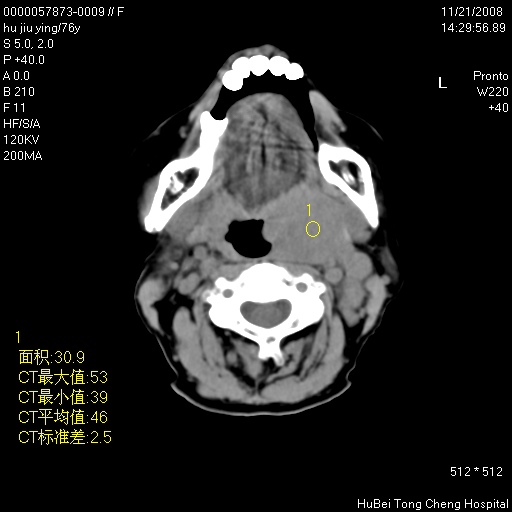

患者 女,76岁。左颈部包块20余天。pe:左侧扁桃体ⅲ度肿大,表面不平,有新生血管,右咽柱红肿,无溃疡。左颈上部包块约3cm×4cm大小,质中等,压痛,边界不清,不能移动。

临床诊断:左侧扁桃体肿瘤?

咽部及颈部ct轴位平扫(层厚、层距均为5mm),图像如下:

左侧咽旁软组织密度肿块影,形态不规则,与周围结构分界欠清,性质待定,建议增强;另双侧上颌窦炎.

左侧咽旁软组织密度肿块影,形态不规则,

与周围结构分界欠清,性质待定,建议增强;

另双侧上颌窦炎.